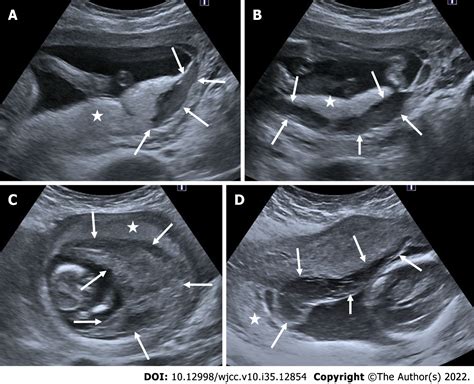

• Transvaginal Ultrasound: This is the gold standard for diagnosing a subchorionic hematoma. The imaging allows the doctor to visualize the size and location of the blood clot relative to the gestational sac.

• subchorionic hematoma pregnancy pictures